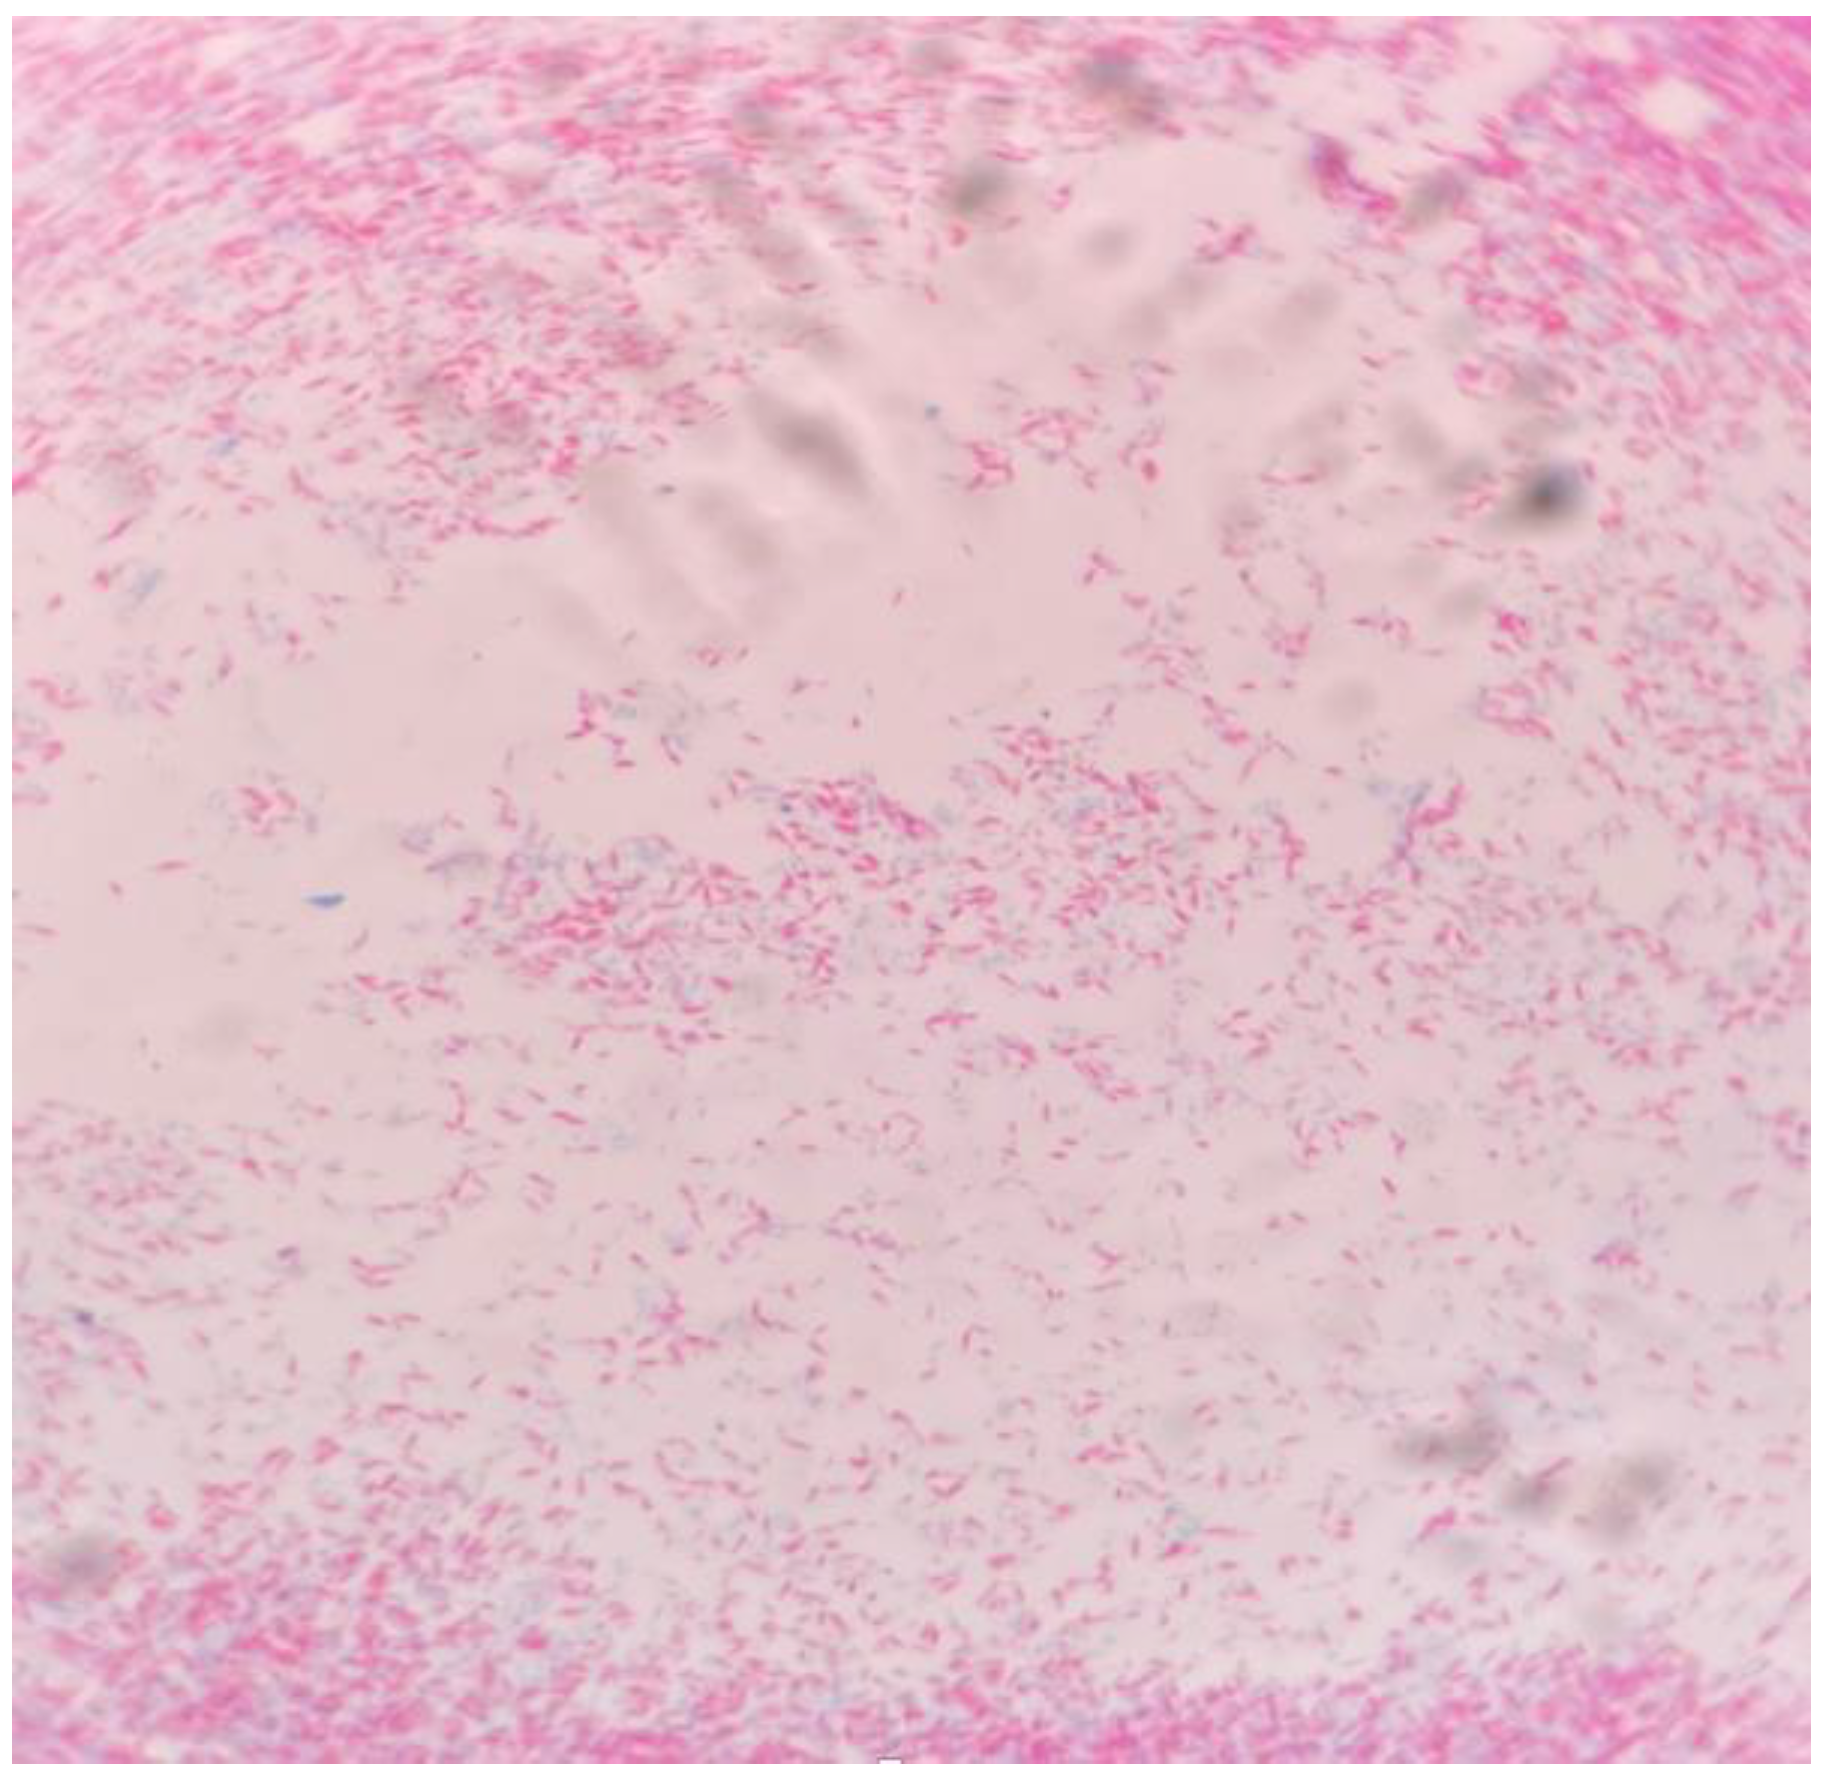

Case 1